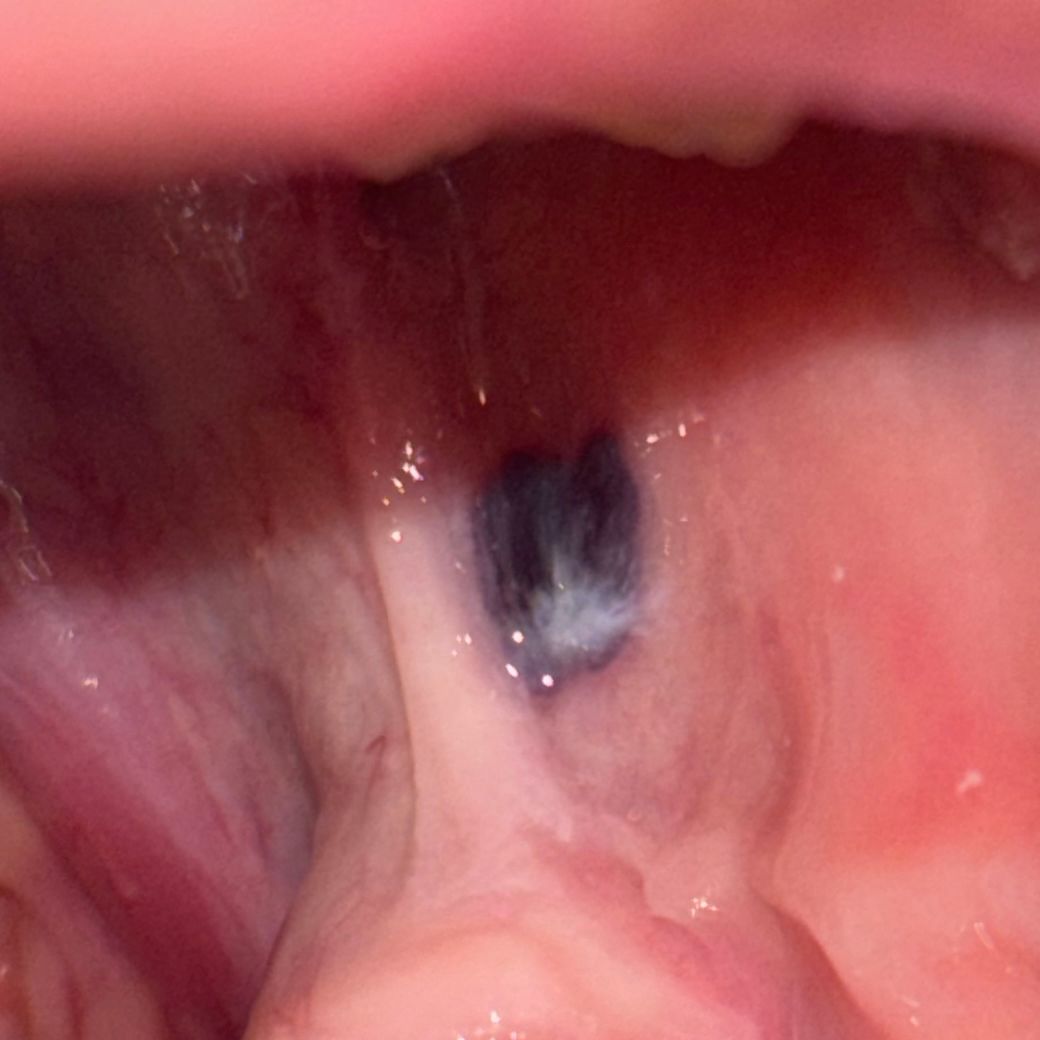

입 안에 검은점이 생겼는데 이게 뭔가요?

사진에 나와있는 것처럼 윗니 아랫니 사이에 검은점이 좀 큰사이즈로 있는데 혹시 병이나 그런건 아니죠? 뭐 때문에 검은점이 생겼는지 궁금해요.

그리고 어떻게 없애야하나요?

• 안녕하세요 치과의사 김철진입니다. 별다른건 아닐꺼 같습니다. 아마도 저부위에 자극을 받아서 피가 뭉쳐 잇는게 아닐까 생각됩니다. 치과에 가셔서 검진을 한번 받아보시는게 좋을것같습니다.

• 혈액종으로 보입니다 혈액종은 구강 전압이 외부 자극에 의해서 손상 받았을 경우 점막 내부에 혈액에 참여가 생기게 됩니다 간단하게 제거할 수 있으며 제거하지 않아도 시간이 지나면서 줄어들게 됩니다 혈액 종이 생기는 원인은 너무 과도한 힘으로 시야를 사용했기 때문입니다 너무 딱딱하거나 음식을 먹을 때 힘을 많이 가하지 않도록 하는 것이 좋습니다